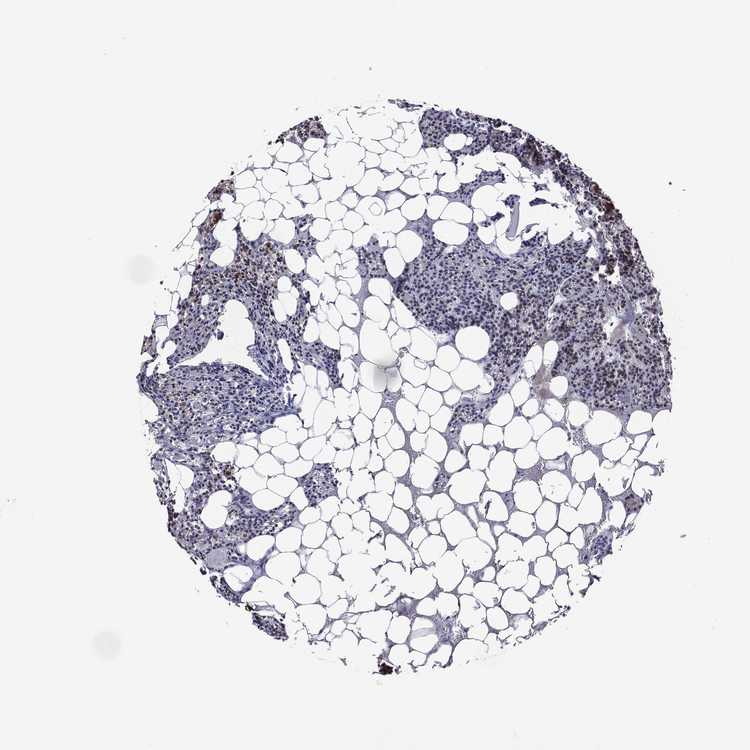

PARATHYROID GLAND - Antibody stainingi

Antibody staining in the annotated cell types in the current human tissue is reported as not detected, low, medium, or high, based on conventional immunohistochemistry profiling in selected tissues. This score is based on the combination of the staining intensity and fraction of stained cells.

Each image is clickable and will lead to virtual microscopy that enables deeper exploration of all samples and also displays staining intensity scores, fraction scores and subcellular localization as well as patient and tissue information for each sample.

Antibody HPA068443

Glandular cells Low